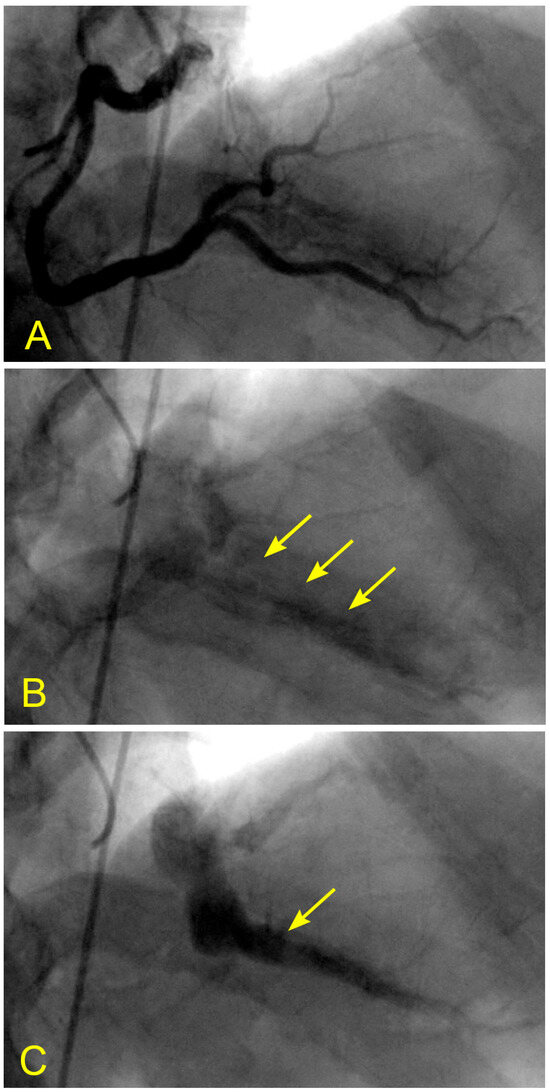

Figure 17.

(A,B) Antegrade flow in the right coronary artery (RCA). These images are in continuous sequence. (A) The artery is completely full of contrast in black. There is a severe 80% lesion in the mid-segment of the RCA (arrowhead). (B) In the ostium of the RCA, the blood, in white, moves in at the beginning of diastole (arrow). (C–F) Antegrade and retrograde flows in the right coronary artery (RCA). (C) Now, the blood, in white, continues to move in at the proximal segment of the RCA (arrow). (D) The blood, in white, reaches the center of the mid-segment where the lesion is located (arrowhead). The contrast looks darker. This is the interface location between the antegrade and retrograde flow at the transition from diastole to systole. (E) The blood, in white, reaches the beginning of the distal part of the mid-segment (arrow). At this location of the transition between systole and diastole, the contrast still looks dark (arrowhead). (F) The contrast looks darker in the mid-segment, and in the proximal segment, the contrast in black looks darker and is at a standstill (red arrow). (G,H) Antegrade and retrograde flow in the right coronary artery (RCA). (G) The blood, in white, reaches the beginning of the distal segment (arrow). At the location of the transition between systole and diastole, the contrast still looks dark (arrowhead). The contrast looks darker in the proximal segment, where the contrast in black is at a standstill (red arrow). (H) The blood, in white, reaches the middle of the distal segment (arrow). At the location of the transition between systole and diastole, the contrast still looks less dark (arrowhead). The contrast looks lighter in the proximal segment (red arrow).

In a similar context, considering the aorta as a tank and the coronary artery as an outflow pipe, the forward movement of coronary blood resembles fluid drainage. During the initial phase of systole, the left ventricle (LV), acting as a proximal valve, contracts, causing the coronary blood to temporarily halt at the distal myocardium. Over time, this results in the accumulation of stationary blood. Simultaneously, the contraction of the LV compresses the myocardial capillary network, forcing the stationary blood to move backward and collide with the anterograde flow, particularly at the transition from diastole to systole. This collision induces turbulence, leading to injury to the intima and promoting the atherosclerotic process (Video S2). Based on the sequence of images illustrating this collision, it suggests many similarities to a water hammer shock event in a pipe (Figure 17A–F).